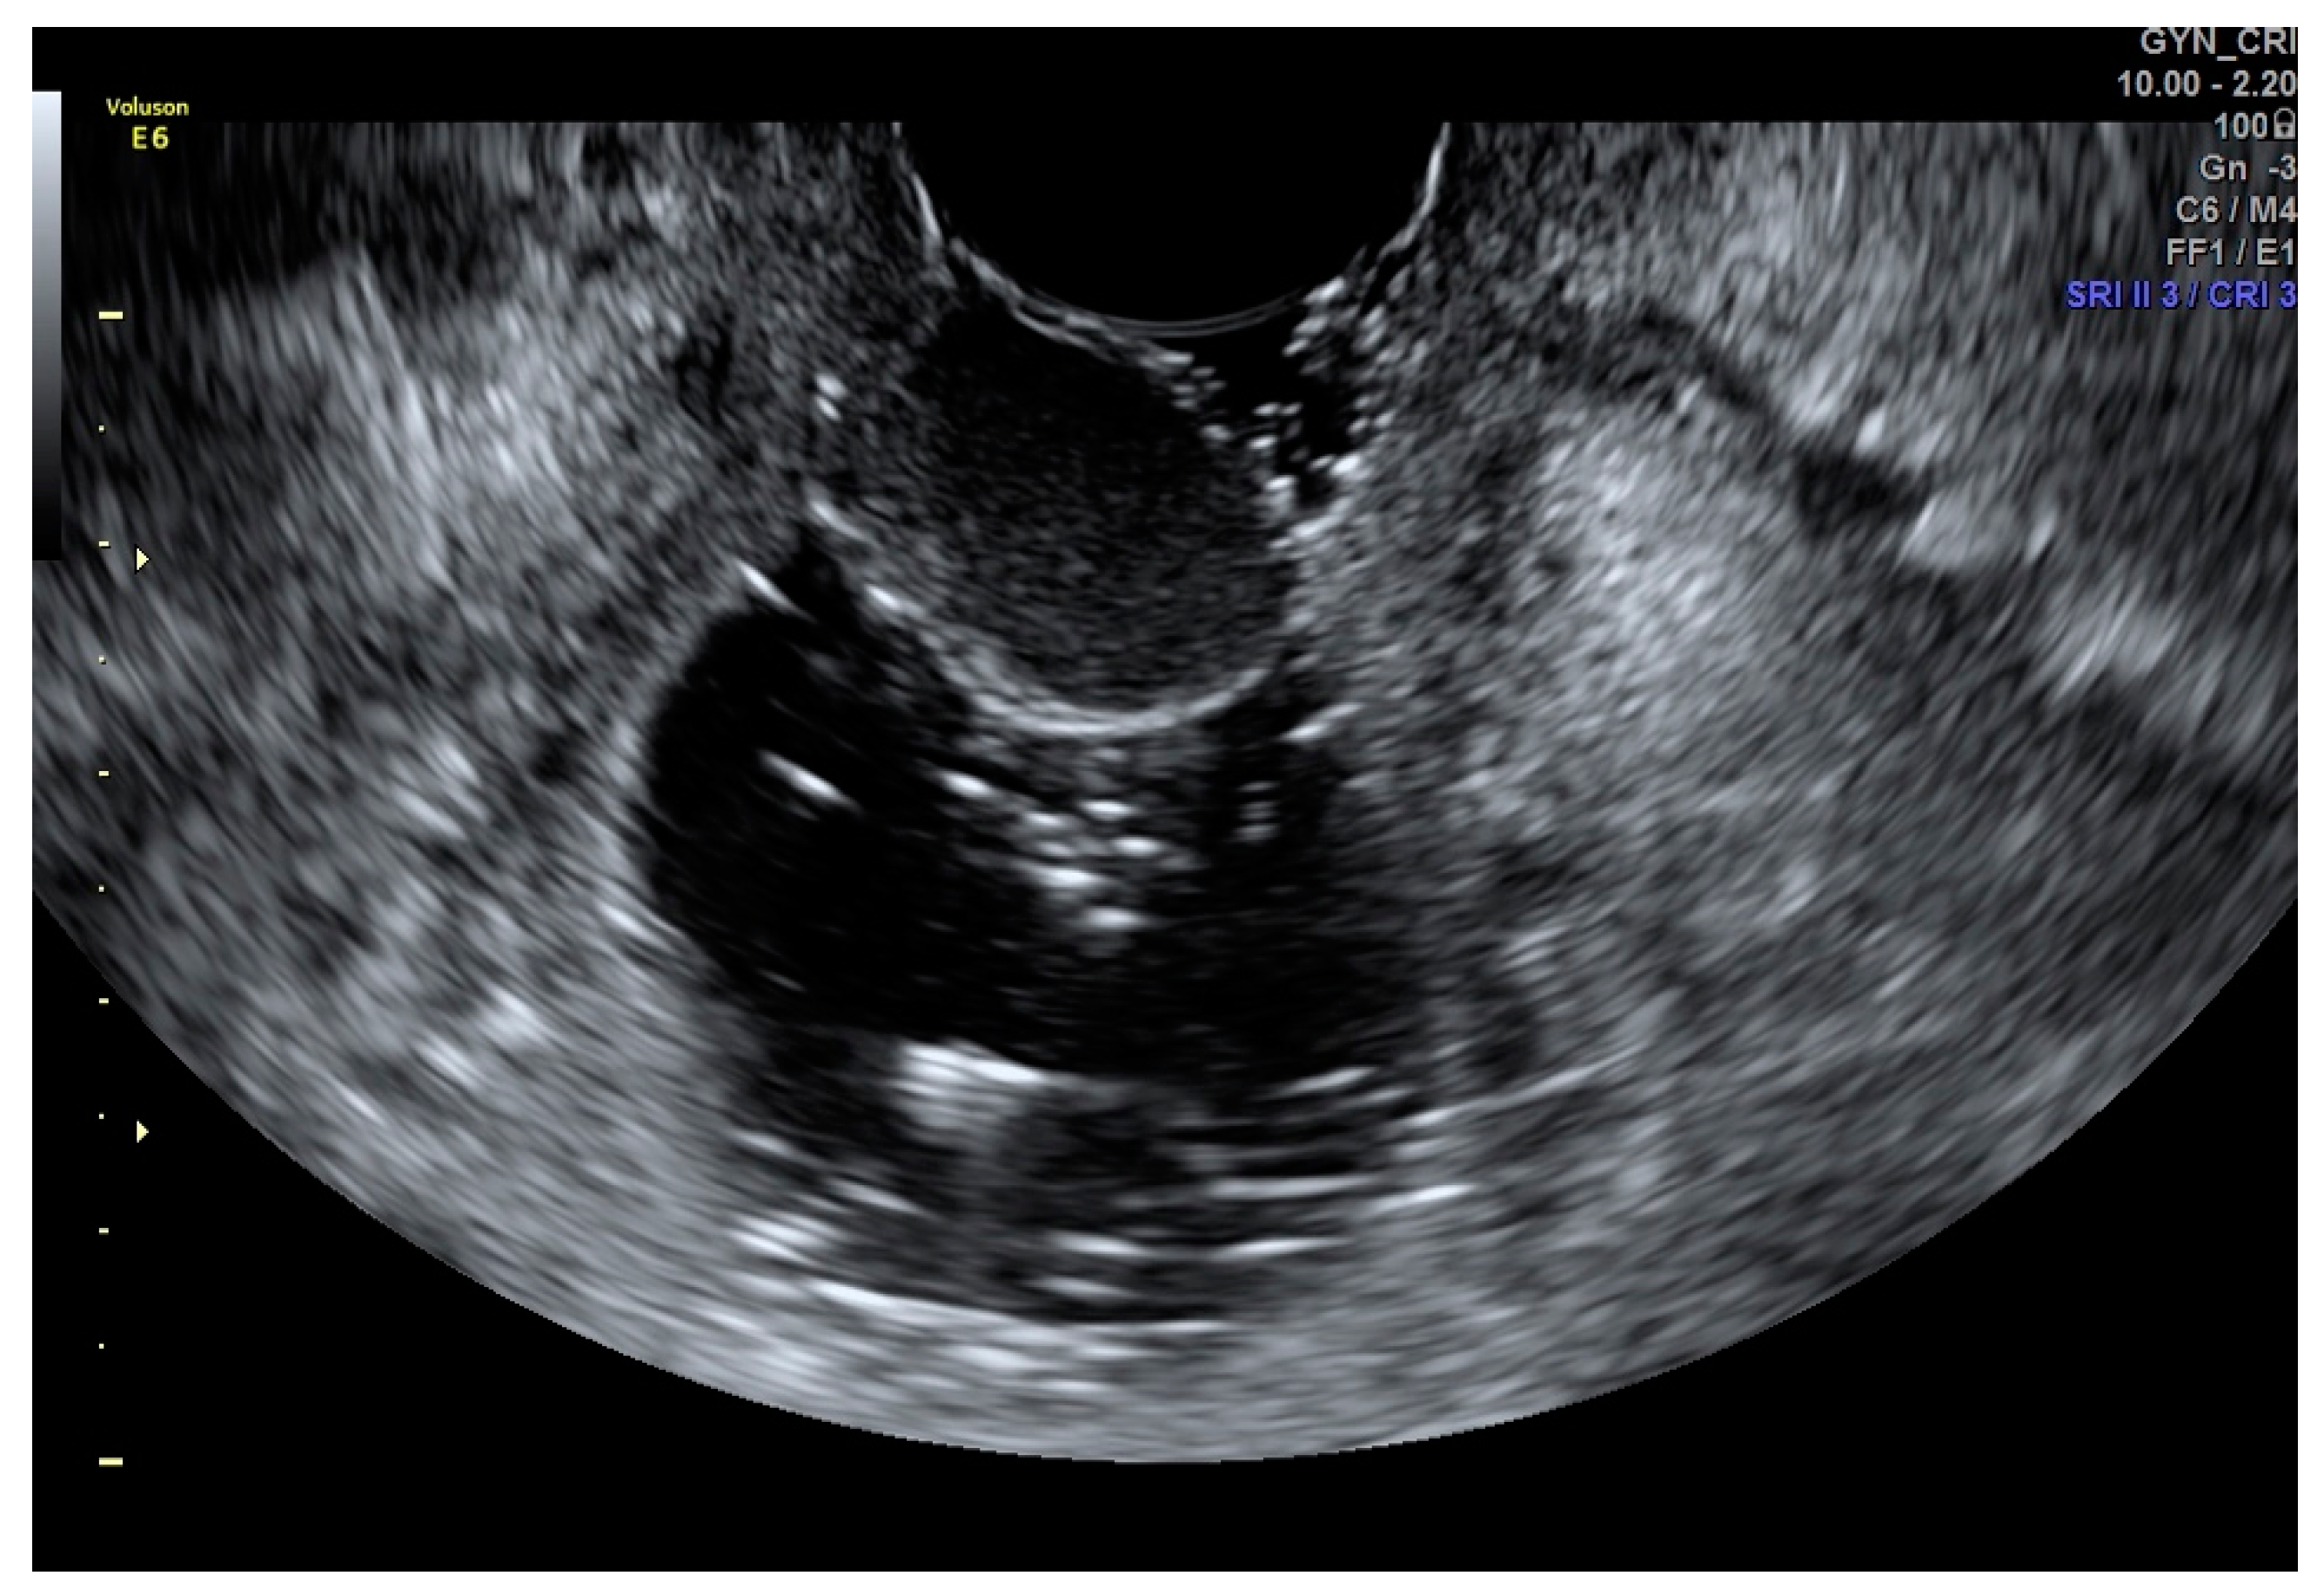

Cervical Cancer

The role of ultrasound in the evaluation of carcinoma has been proven efficient by several studies. Due to the fact that the vaginal walls are collapsed, their similar echogenicities, which reduce the contrast resolution, limit the discrimination between cervical cancer and the vagina, making the ultrasound evaluation of exophytic early-stage cervical cancer often difficult [23,24,25].

Although there are no studies in the literature to date, SVG may be a simple and cheap procedure for the evaluation of patients with mostly exophytic early cervical cancers when TVS alone is not adequate for the correct assessment of the tumour, its size, and its fornices infiltration (Figure 3 and Figure 4).

Figure 3. SVG image of an exophytic cervical cancer lesion (Panel (A)) and its vascularization (Panel (B)).